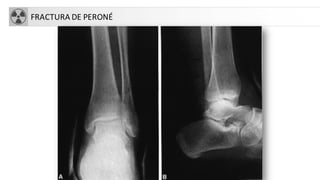

FRACTURA DE PERONÉ

FX DIAFISARIAS: TIBIA-PERONE

• Fx tibia: donde más fracturas abiertas se producen

• Fx peroné

FRACTURASDE TOBILLO

• Fracturas en supinación-rotación externa (60%)

• Fracturas en supinación-aducción (20%)

• Fracturas en pronación-rotación externa y pronación-

abducción (20%)

• Fracturas en pronación-dorsiflexión.

• A. Fractura unimaleolar (de tibiao

peroné)

• B. Fractura bimaleolar

• C. Fractura equivalentebimaleolar

• D. Fractura trimaleolar

• TratamientoQuirúrgico: En lesiones

de dos complejos, fracturas

inestables o desplazadas. Resto: tto

conservador